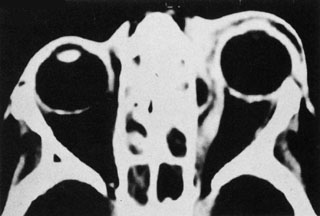

Magnetic resonance imaging (MRI) is purported to be more useful than CT in the diagnosis of preseptal cellulitis. It is less reliable at diagnosing the subtle signs of muscle enlargement and periscleritis and thus is not as useful in differentiating orbital cellulitis from other inflammatory orbital diseases.71 On MRI with gadolinium contrast, orbital cellulitis may show a smearing or linear streaking of the normal fat shadows on T2-weighted images. MRI is excellent for demonstrating localized fluid collections such as abscesses. It is not helpful in distinguishing a transudate from an exudate, because both appear liquid and are of low intensity on T1-weighted images and bright on T2-weighted images (Fig. 19).

Fig. 19. Magnetic resonance image of preseptal cellulitis with anterior abscess formation.

MRI is superior to CT in the diagnosis of cavernous sinus thrombosis. T2- and proton-weighted images show high signal luminal narrowing as well as absent flow or localized parenchymal infarcts (Fig. 20).72 Absent flow can be demonstrated as well in the superior ophthalmic vein in cases of carotid or cavernous sinus thrombosis.72 MRI with gadolinium can help define these abnormalities and can detect dural invasion.

Fig. 20. Cavernous sinus thrombosis. Axial T1 image shows cavernous carotid luminal narrowing on right and enlargement of right cavernous sinus. Note extensive sinus disease.